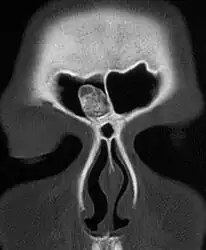

Medical imaging such as X-ray, CT scan and MRI show dense, clearly defined, round white tumors attached to bone.[1] They may be diagnosed when having medical imaging for another reason.[3] Osteomas of the paranasal sinuses and skull base can be diagnosed using CT-scan without intravenous contrast, allowing its size and relation to nearby important structures to be assessed.[3] A biopsy is not usually required.[3]

CT-scan skull: Osteoma of the frontal sinus -